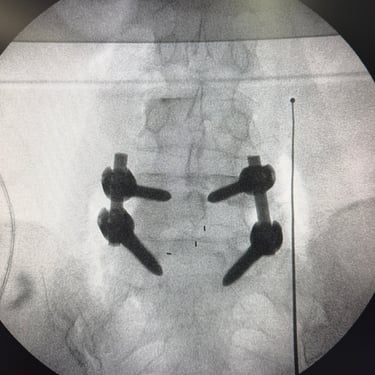

Listesis Lumbar L5–S1: Estabilización Vertebral con TLIF

La listesis lumbar L5–S1 es una afección en la que una vértebra se desliza sobre otra, provocando inestabilidad, dolor lumbar y, en muchos casos, compresión de las raíces nerviosas. Cuando el tratamiento conservador no logra controlar los síntomas, la fusión intersomática transforaminal (TLIF) se presenta como una opción quirúrgica efectiva. Este procedimiento permite descomprimir las estructuras nerviosas, restaurar la alineación vertebral y lograr una fijación sólida mediante tornillos transpediculares e injerto óseo. La técnica TLIF reduce el dolor, mejora la estabilidad de la columna y favorece una recuperación funcional progresiva y segura.